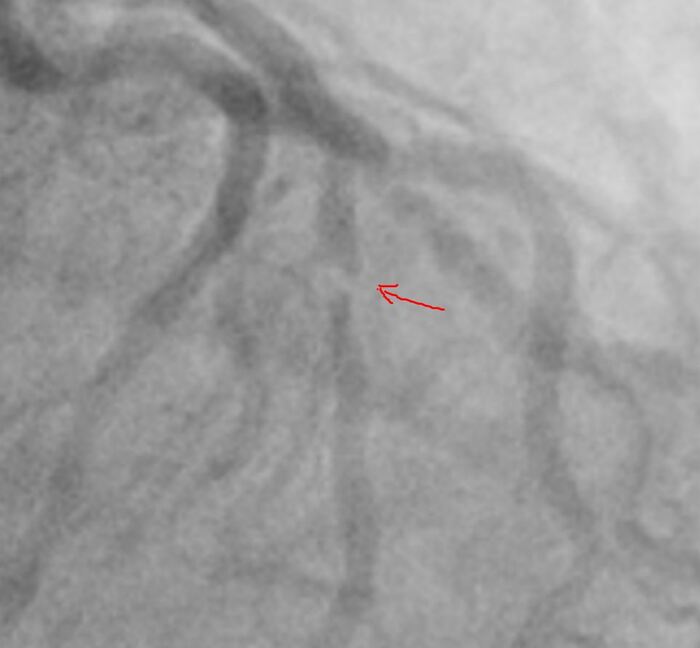

Итак на коронарографии такая картина при первой же съемке:

Стенозирование передней межжелудочковой артерии (ПМЖА) в начальном (проксимальном сегменте), инфаркты при полном закрытии ПМЖА в этом сегменте часто фатальные, либо приводят к инвалидизации